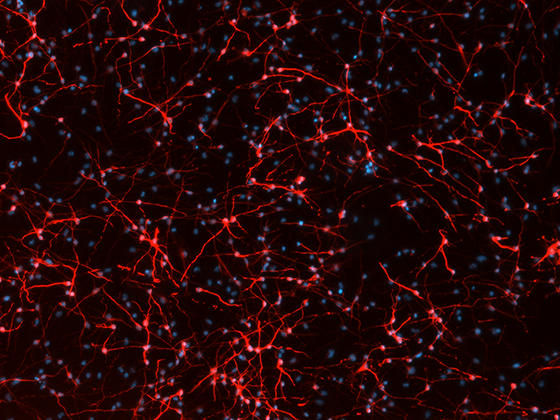

Differentiation of neural stem cells into neuronal networks (red, betaIII-tubulin) in vitro is stimulated by mesenchymal stem cell-secreted factors. DAPI as nuclear counterstain. Courtesy of Sara De Palma.

Besides MSCs, we also explore the use of neural stem cells and the use of crucial growth factors like IGF1 as regenerative strategies to improve neurodevelopment after neonatal brain injury. Furthermore, we are aiming for combination therapies with stem cells and nutrition (see also the research line Nutraceuticals for the developing brain).